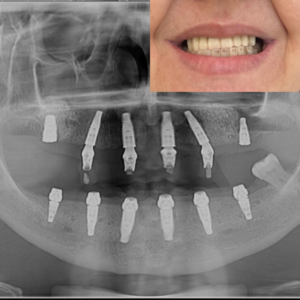

La 24-48 de ore după intervenție, pacientul revine pentru fixarea danturii provizorii pe implanturi. Lucrarea temporară este ajustată pentru a se potrivi perfect și pentru a asigura un zâmbet estetic și funcțional imediat. Această proteză temporară va fi purtată timp de aproximativ 6 luni, perioada necesară vindecării implanturilor. În această etapă, medicul oferă și instrucțiuni post-operatorii detaliate pentru îngrijirea corectă a danturii provizorii și a implanturilor pe durata procesului de vindecare.